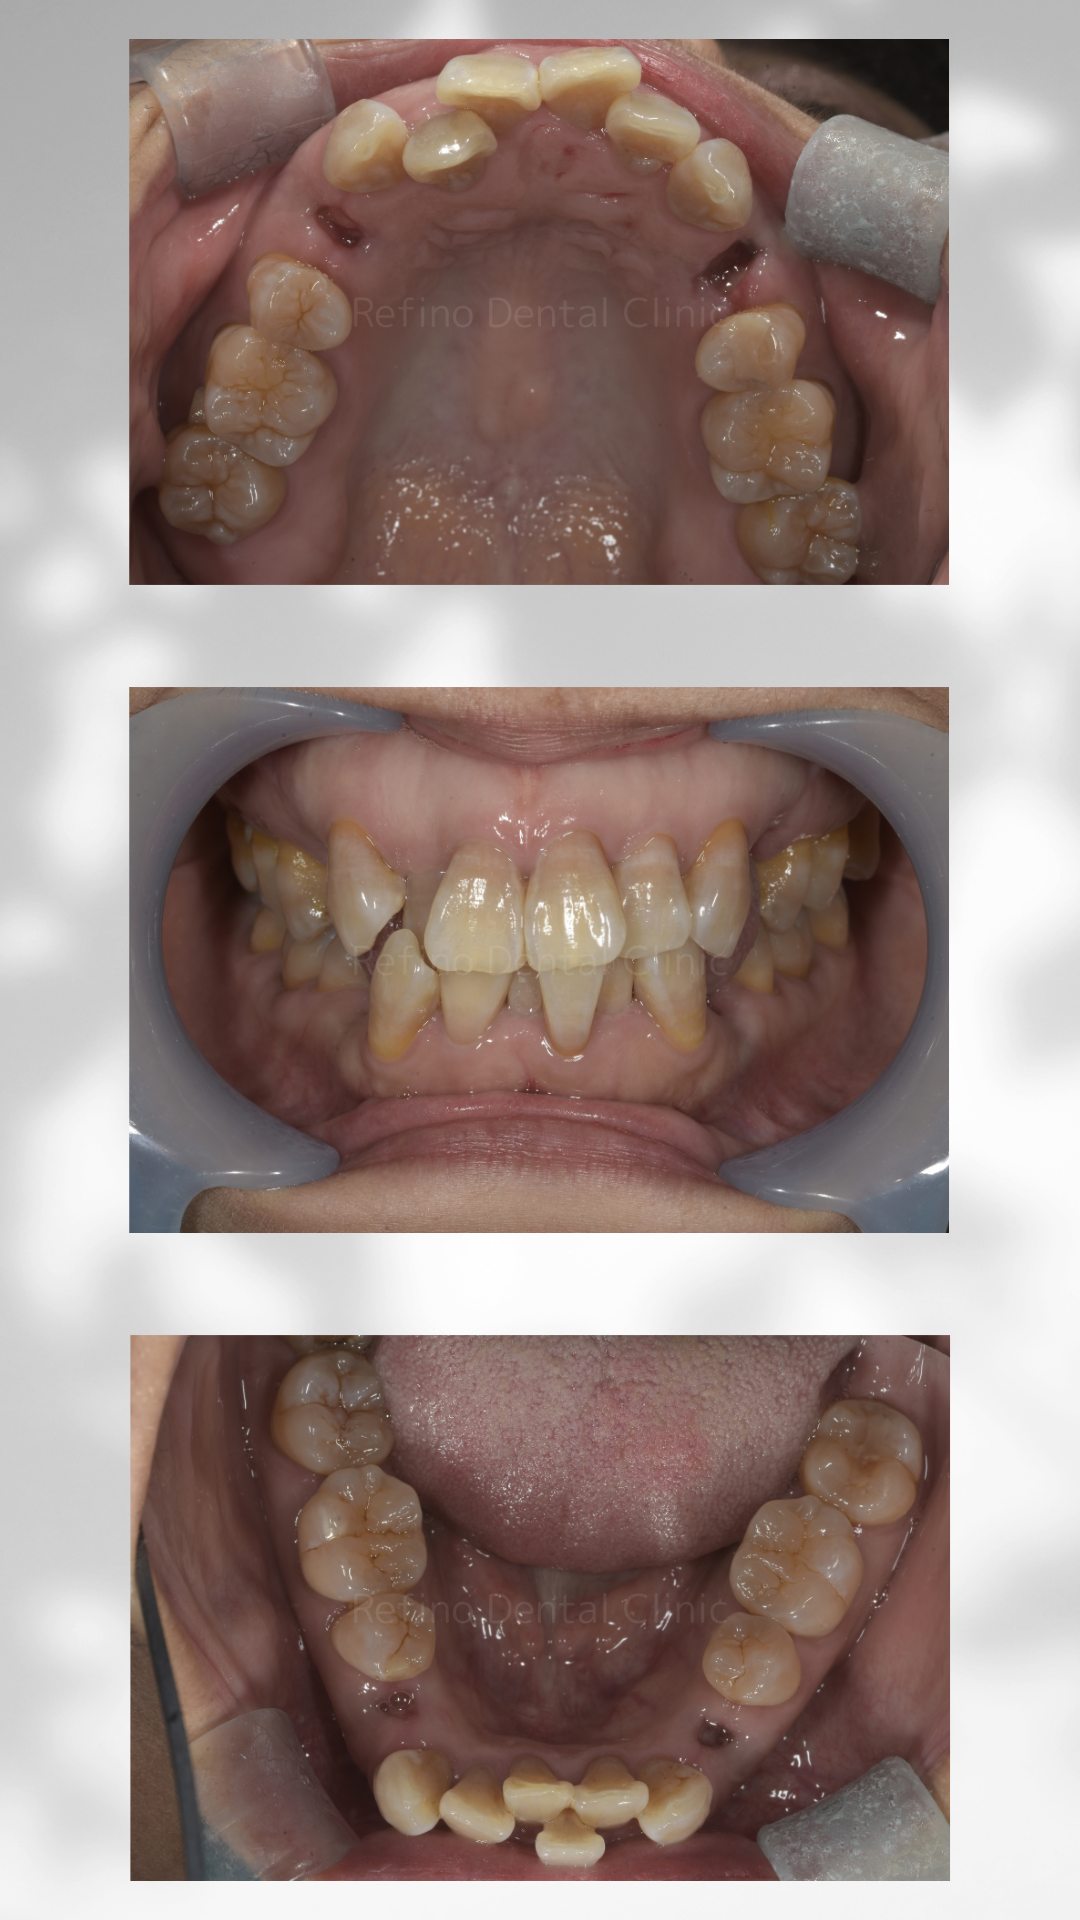

症例紹介

【治療経過】上下のガタガタ歯並びをマウスピース矯正で治療を行った症例

Before

| 診断 | 上下顎叢生 | ||||

| 処置内容 | マウスピース矯正 上下顎第一小臼歯抜歯 クリアコレクト使用 |